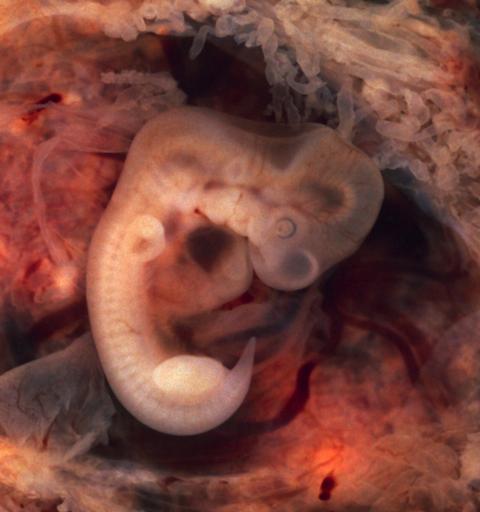

MAKE A MEME View Large Image Tubal Pregnancy with embryo.jpg Human Embryo 7th week of pregnancy 5th week p o This photo of an opened oviduct with an ectopic pregnancy features a spectacularly well preserved 10-millimeter embryo It is uncommon to see any embryo at all ...

Keywords: Tubal Pregnancy with embryo.jpg Human Embryo 7th week of pregnancy 5th week p o This photo of an opened oviduct with an ectopic pregnancy features a spectacularly well preserved 10-millimeter embryo It is uncommon to see any embryo at all in an ectopic and for one to be this well preserved and undisturbed by the prosector's knife is quite unusual Even an embryo this tiny shows very distinct anatomic features including tail limb buds heart which actually protrudes from the chest eye cups cornea/lens brain and prominent segmentation into somites The gestational sac is surrounded by myriad chorionic villi resembling elongated party balloons This embryo is about five weeks old or seven weeks in the biologically misleading but eminently practical dating system used in obstetrics The photo was taken on Kodak Elite 200 slide film with a Minolta X-370 camera and 100mm f/4 Rokkor bellows lens at near-full extension The formalin-fixed specimen was immersed in tap-water and pinned to a tray lined with black velvet The exposure was 1/4 second at f/8 http //www flickr com/photos/euthman/304334264 First published October 12 2001 Ed Uthman MD http //www flickr com/photos/euthman/ Flickr Wikipedia Euthman Assessments 1 Image Tubal Pregnancy with embryo jpg 1 1 Gross pathology Ectopic pregnancy Human embryos